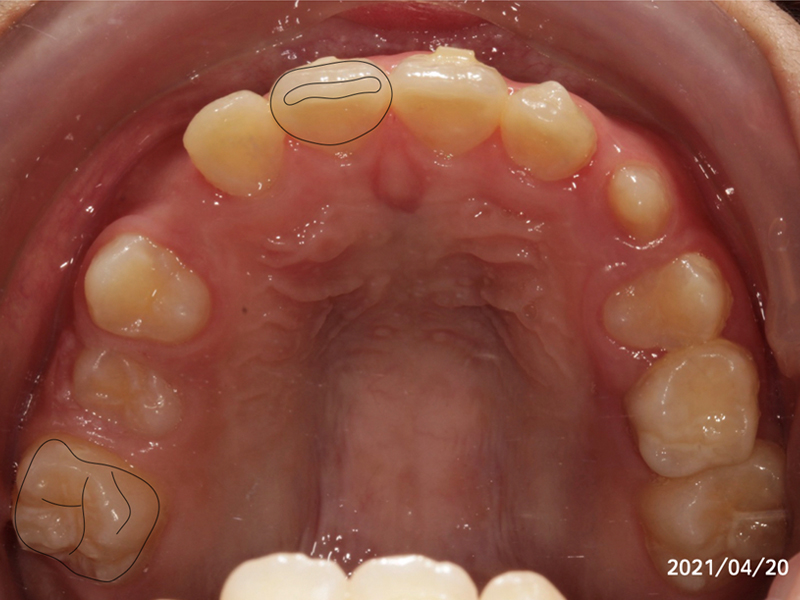

我們利用兒童隱適美幫 Kevin 擴弓

左圖是進行兒童隱適美的療程一年後,我們看到 Kevin 的變化。

黑色標示處是兩顆恆牙,分別是右側正中門牙,與右上第一大臼齒。按照 Kevin 的生長來看,如果在完全未介入的情況下,原先三顆乳牙的地方,要排入四顆恆牙,會有嚴重的空間不足。因此可以預期 Kevin 的犬齒會從上方牙齦中冒出來。(也就是俗稱的高位虎牙)

令人欣喜的是:我們幫Kevin的牙弓擴開至少了1.5顆恆牙的寬度,讓Kevin的所有恆牙都有足夠的空間都能朝理想的位置生長。